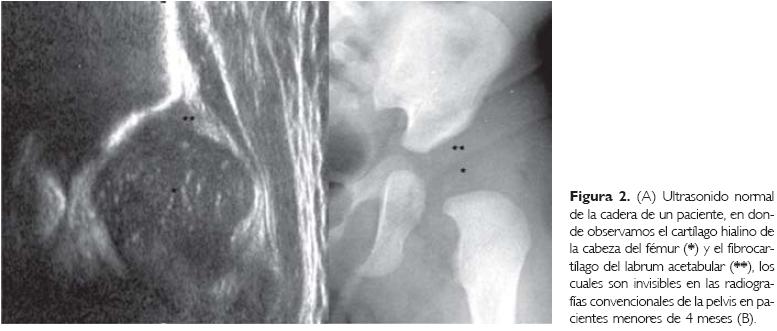

El uso del ultrasonido para la valoración de las enfermedades del sistema músculo-esquelético, se ha extendido rápidamente debido a su capacidad para identificar los tegumentos, el cartílago hialino, el fibrocartílago, los músculos y el líquido intraarticular. Otras ventajas de este método son: la posibilidad de hacer estudios dinámicos en tiempo real y que no produce radiación ionizante.1-4 En el caso específico de la cadera infantil, el ultrasonido permite estudiar el cartílago hialino de la epífisis proximal del fémur (cabeza femoral), aun cuando ésta no es visible en las radiografías convencionales antes de los cuatro meses de edad,2,5,6 la forma del techo y el borde externo del acetábulo, la forma y posición del fibrocartílago del la-brum acetabular (también no visible en radiografías), el espacio articular coxofemoral y la porción lateral de los músculos glúteos menor y mayor.2,7,8

El techo del acetábulo, al articularse con la cabeza del fémur, habitualmente tiene una forma cóncava o levemente plana con un borde lateral anguloso. En presencia de displasia de la cadera, el acetábulo adquiere una forma convexa con el borde lateral redondeado, incluso aquí pueden formarse muescas producidas por el apoyo anormal de la cabeza femoral (Figs. 2, 3, 4 y 5).1,2,6-8,13,19